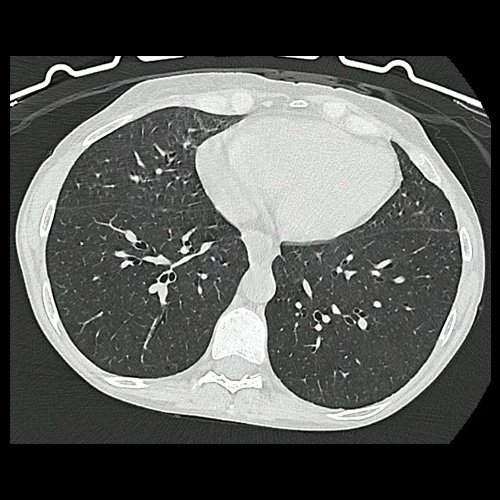

• TAC de tórax con protocolo para EPID (02/06/25): se compara con estudio previo con fecha de 01/2025. No se identifican signos de consolidación del parénquima pulmonar o derrame pleural. Bulla intraparenquimatosa basal izquierda. Respecto del estudio previo se encuentra disminuido el infiltrado micronodulillar en el segmento lingular inferior, respecto del estudio previo, no visualizándose en este examen, probablemente de origen inflamatorio-infeccioso. Persisten micronodulillos centrolobulillares sutiles e inespecíficos en lóbulo superior del pulmón derecho principalmente y un ténue patrón micronodulillar en el resto de los campos pulmonares, muy sutil, sin cambios con respecto al estudio anterior. En los registros en espiración se observa colapso parcial del espacio aéreo con signos de atrapamiento. Tráquea y bronquios permeables. Secuelas pleuroparenquimatosas biapicales. Con ventanas para la valoración del mediastino se observan múltiples estructuras ganglionares mediastinales de tamaño conservado. Silueta cardíaca respetada. Esófago con contenido líquido en su interior. No se observan adenomegalias axilares. No se identifican lesiones focales en el abdomen superior, destacando hepatoesplenomegalia con un bazo accesorio y lo que podrían corresponder a múltiples estructuras vasculares de circulación colateral y shunt esplenorrenales, que sería útil cotejar con contraste endovenoso. Las estructuras óseas muestran incipiente espondiloartrosis dorsal.

TAC de tórax con protocolo para Enfermedad Pulmonar Intersticial Difusa (EPID). Corte axial (02/06/25)